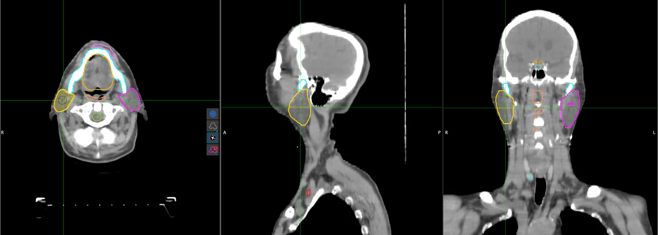

Contour CoPilot allows users to quickly draw and edit target volume contours and organs at risk contours, whether those were drawn manually or auto-generated via an AI segmentation platform such as Contour ProtégéAI+™. The advantage of CoPilot lies in its swift, accurate predictive contour rendering on each upcoming slice by factoring in the user’s previous edits while utilizing a deformable registration algorithm.

Many of our customers who love Contour CoPilot suggested that a deformable interpolation would further increase time savings on contour creation and editing, and we responded. MIM’s new Contour CoPilot with Interpolation does just that. Imagine the predictive quality you have come to expect with Contour CoPilot applied to multiple slices with the same accurate intensity detection, effectively multiplying your time savings. With this new tool, the entire contouring process becomes refreshingly easy. Clinicians have been impressed with how the Contour CoPilot with Interpolation tool augments efficiency in their OAR and TV contouring protocols.